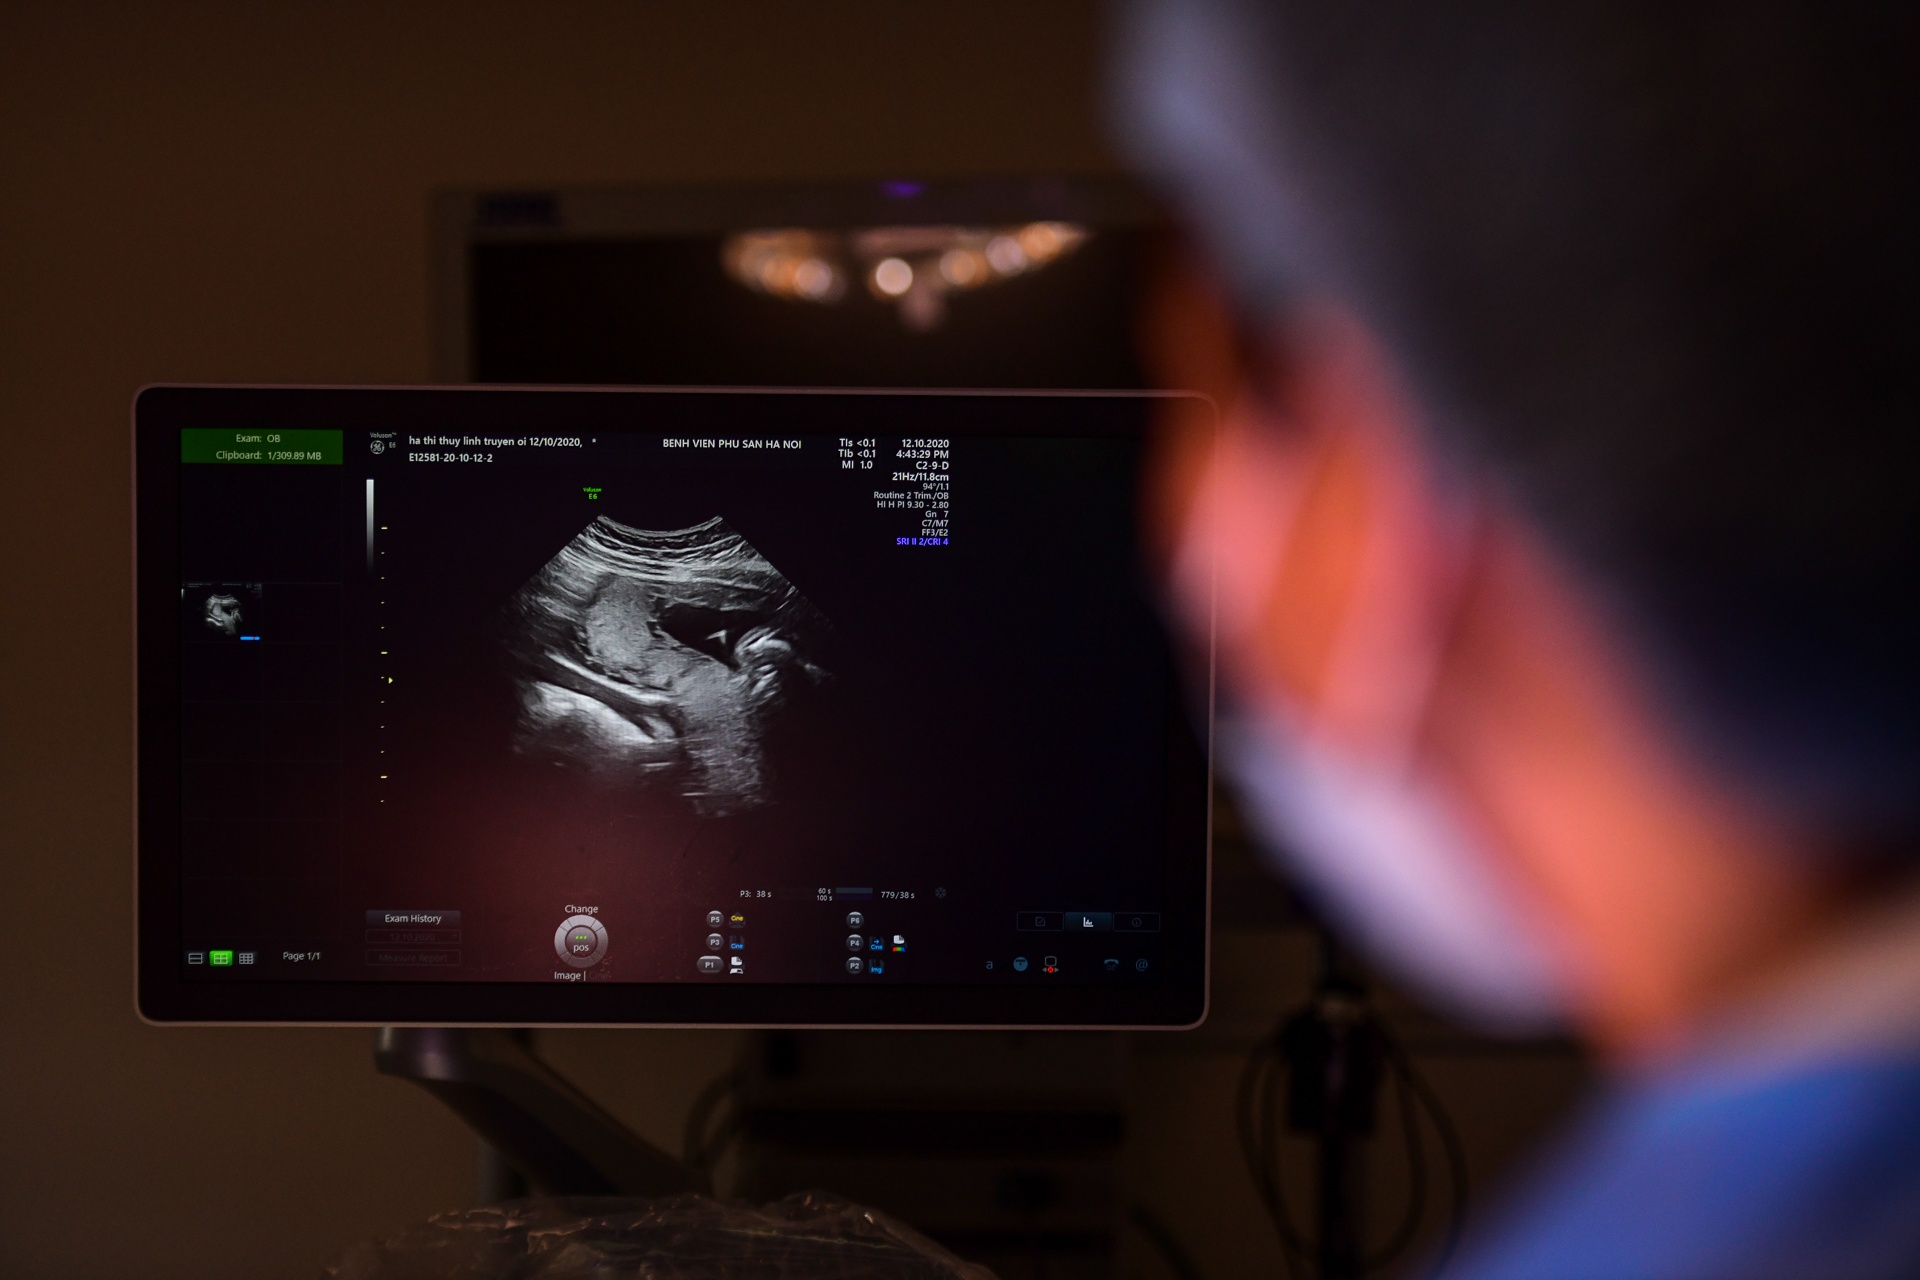

Bác sĩ cứu thai nhi còn nằm trong bụng mẹ

Can thiệp bào thai là phương pháp hiện đại giúp cứu thai nhi gặp nguy hiểm trong bụng mẹ.

Trước đây, với thai nhi bất ổn, bác sĩ chỉ biết lắc đầu và đứng nhìn em bé ra đi. Hiện nay, bác sĩ có thể đưa dụng cụ vào bụng thai phụ, can thiệp cứu sống em bé. Nhớ đó, thai nhi thoát khỏi tình huống nguy hiểm, tiếp tục phát triển trong bụng mẹ đến lúc đủ ngày đủ tháng.

- Thông thường nhắc tới sản khoa, người ta chỉ nghĩ đến việc bác sĩ khám thai, mổ, đỡ đẻ. Tuy nhiên, sản khoa giờ hiện đại hơn với y học bào thai khi bác sĩ không chỉ khám mà còn có thể chữa bệnh cho thai nhi thay vì để trẻ tử vong hoặc ra đời cùng nhiều dị tật.

Tất cả dụng cụ y sinh hiện đại đã giúp các bác sĩ can thiệp buồng ối, sửa chữa những hội chứng gây tử vong cho thai nhi. Đội ngũ y tế sẽ thực hiện kỹ thuật này bằng việc đưa dụng cụ vào buồng ối để can thiệp, sau đó đóng lại, chờ thai tiếp tục phát triển đến đủ tháng.